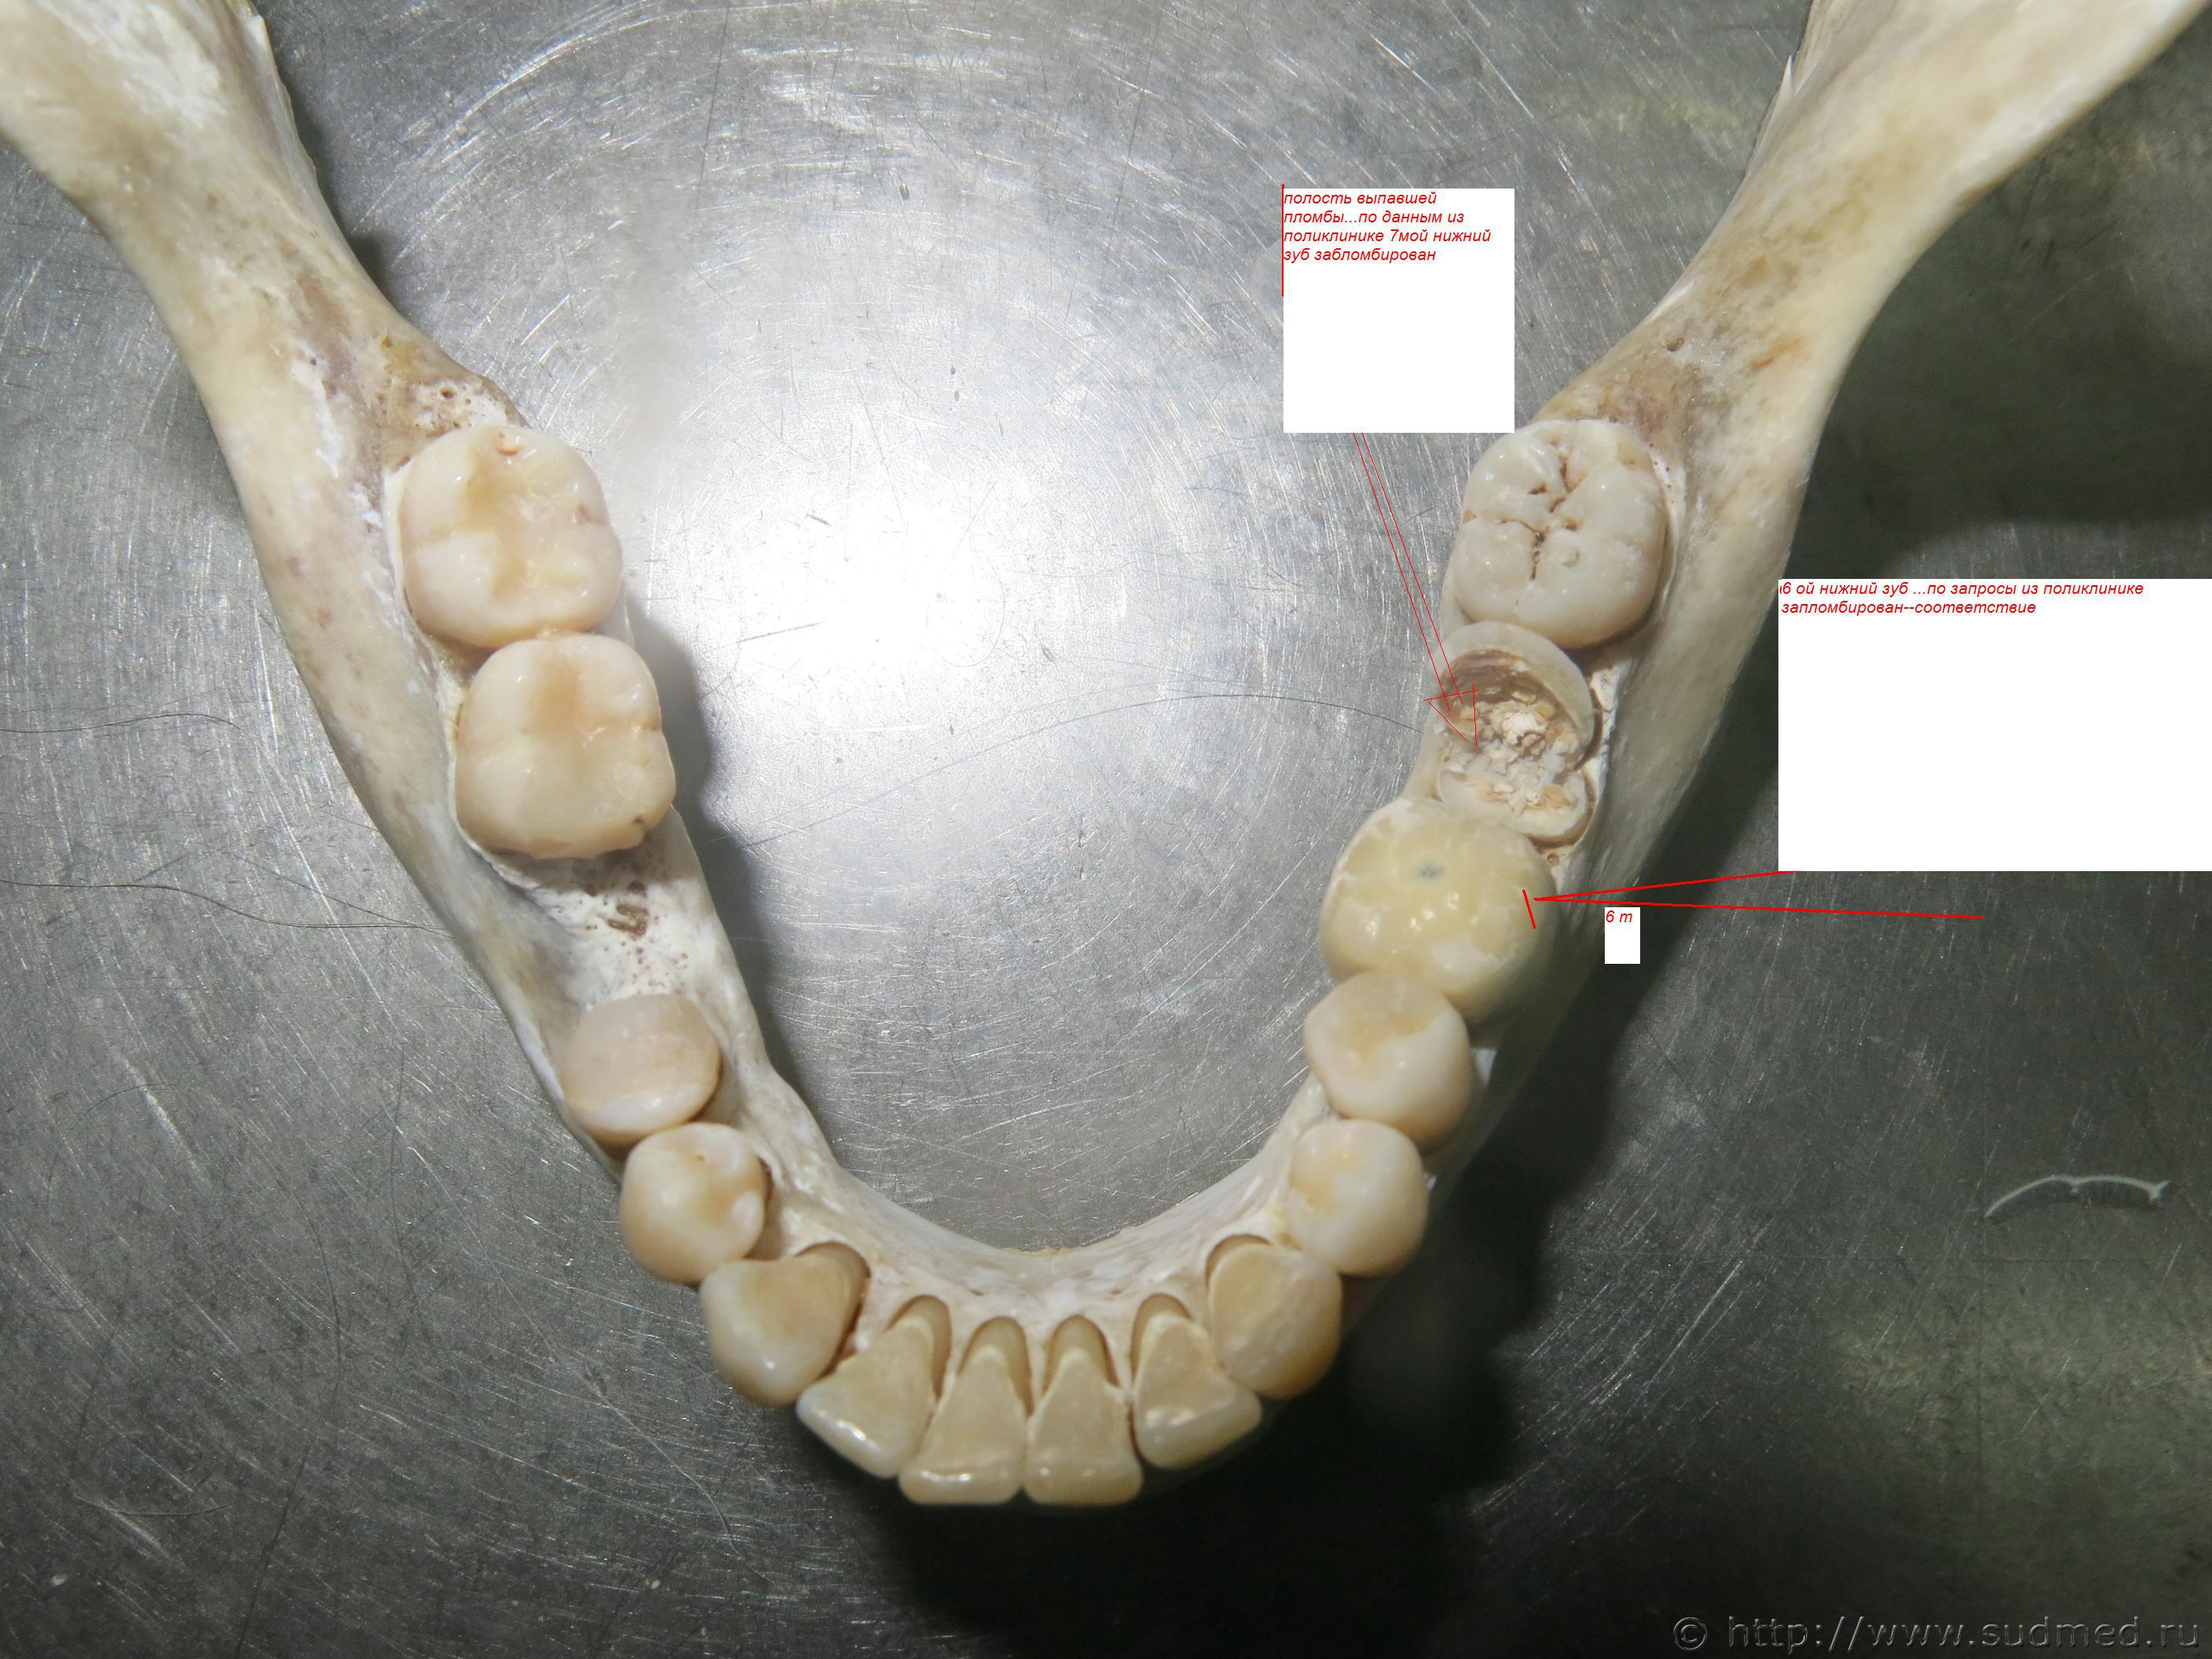

здравствуйте уважаемые эксперты..год назад пропала моя бывшая гражданская жена..загадочно среди ночи ..находясь у подъезда своего дома из центра москвы...через 3 месяца в газете ..егорьевский курьер..появилась заметка об обгоревшем трупе на обочине дороги....все признаки описания включая скол на зубе..рост..цвет волос...размер ноги..соответствовал пропавшей..в чем согласились со мной и местные оперативники..кстати они даже приезжали после в москву для дознания..далее в егорьевске мы сдали на днк материал ее матери...после этого все пропали..мы с трудом только в июле дозвонились..до следователя ск...которая в устной форме сказала что анализ отрицательный...мне удалось с помощью своего овд из зубной поликлинике взять схему ее зубного ряда..все пломбы оказались в соответствии с фото зубного ряда трупа...а далее в ее квартире мы обнаружили ее выпавшию зубную пломбу..полость которой целиком соответствовала полости разрушенного зуба трупа...см фото..с этими материалами я нанес визит к следователю в егорьевск...которая разговаривала со мной бесцеремоно ..ссылаясь на днк -экспертизу..отказалась приобщать мои материалы...сказала что днк трупа есть в базе..и мы сами может продублировать...и еще я узнал что уд в производстве по111 ч 4!!!!! и смерть наступила предположительно от ожогов!!! хотя когда я приезжал в овд мне сказали что причина смерти асфиксия и труп перед тем как сожгли продержали около месяца замороженнным поэтому огонь его не брал...после этого мне стало понятно что следователь не заинтерисован в опознании..выводы днк теста она мне показала сделана на ул щепкина 61...возможно ли фальсификации при днк-экспертизы? каким образом...уверенность что труп наш есть...

официальный заявитель по исчезновению ее мать...потерпевшая в течении долгого времени была моей гражданской женой...в последнее время вела асоциальный образ жизни...ночью возращалась с пьянки из соседнего подъезда..99 процентов что ее затолкали в машину как сексуальный объект и увезли...наш розыск никакого раследования не проводил...я ее искал сам как мог...еженедельно ходил в брнс..пока ни наткнулся на труп в егорьевске...местные оперативники мне рассказали что труп прежде чем сжечь и выбросить на обочине продержали значительное время...в холоде..поэтому он был задубевший и огонь его не брал...причиной смерти была определена асфиксия....об этом даже было упомянуто в брнс...читать экспертизу мне никто не дал естественно..уд возбуждено 27.01 2015 овд егорьевского района..в середине февраля труп был звхоронен а череп сохранен..все фото мне были присланы на почту..меня опрашивали в овд достаточно долго оперативники не следователь...вообщем они поняли что из москвы зацепок никаких нет..! хотя все были единогласны с тем что это она...узнал про 111?подсмотрел у следователя когда напросился на прием 2 недели назад..там было указано что смерть предположительно на ступила от ожогов ..а не асфксии!!!! материалы которые я нарыл по зубам никто даже смотреть не стал....затем зашел к оперативникам показал эту картинку с пломбой..они согласились что таких совпадений не бывает..но у следователя днк а это важнее..они и продиктовали мне дело номер 50657 и статья 111ч 4